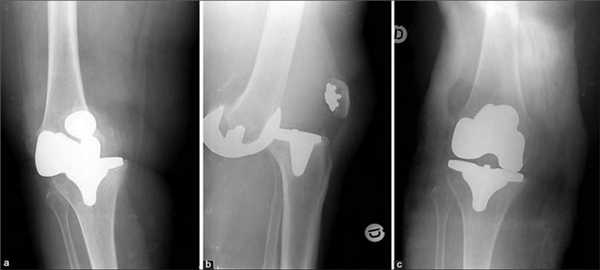

Типы протезов и связанные с ними методики

Вы уже знаете, что бывает полное и частичное эндопротезирование коленного сустава, где в первом случае лечение подразумевает полноценную замену суставных поверхностей, а во втором - имплантацию поврежденного участка одного из мыщелков. Соответственно, протезы классифицируются на тотальные, одномыщелковые и ревизионные для замены импланта.

- После постановки однополюсной системы максимально сохраняется собственный костно-хрящевой сегмент и не затрагиваются связки, кстати, они должны быть в хорошем состоянии.

Одномыщелковая замена сустава на рентгене.

Сравнение двух типов операций.

С каждой последующей операции статистика успешности ниже. Импланты при этом становятся все более громоздкими.

Одномыщелковое протезирование подразумевает срок службы небиологического устройства максимум 7 лет. Тотальное замещение предусматривает время службы вживленного механизма от 15 лет. Ревизионное переносится сложнее, а риск инфекции и других негативных явлений почти в 2 раза выше, чем после первичной операции.